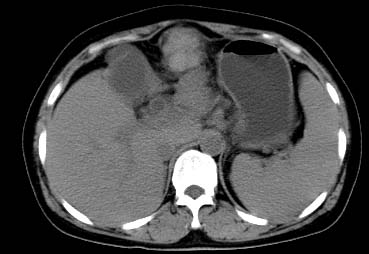

以下是引用西北一只狼在2008-6-30 20:58:00的发言:[br]肝左叶胆管细胞ca并肝门淋巴结转移、胰腺、胃小弯浸润

以下是引用ydx_74在2008-6-30 21:54:00的发言:[br]左叶胆管细胞ca并肝门淋巴结转移、胰腺、胃小弯浸润